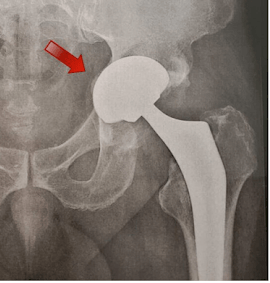

RX evidenciando fraturas peri-protéticas do fêmur a esquerda e do acetábulo a direita.

Essa complicação é extremamente infrequente, mas quando ocorre é grave. É quando existe uma fratura, seja na bacia ou no fêmur, ao redor de um dos componentes da prótese.

Ela pode ocorrer:

Durante a cirurgia: geralmente por um erro técnico, causando a fratura no fêmur ou no acetábulo, durante a colocação da prótese

Na fase inicial após a cirurgia: por apoiar muito o peso do corpo na perna operada ou por alguma queda

Tardiamente após a cirurgia: consequência de uma queda; a presença de soltura da prótese aumenta o risco dessa complicação ocorrer